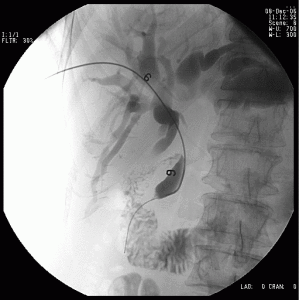

剛果紅(2)瘺管造影:是更可靠更直接的檢查方法。從瘺口插入一根細塑膠導管,瘺口用金屬物作標誌。從導管注入造影劑如泛影葡胺,12.5%碘化鈉或碘油等,同時在螢光屏上觀察造影劑的走向。此時可調節導管插入深度,造影劑注入數量和病者體位。挑選合適時間攝片,並在幾分鐘後可重複攝片,據以了解瘺管長短,通向何段腸道,有無膿腫存在等。